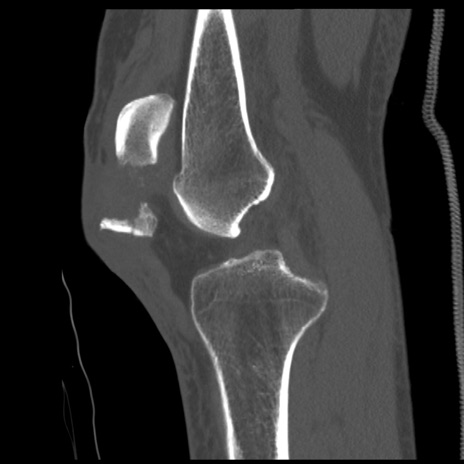

症例28 右膝関節CT(矢状断像)

右膝関節CT